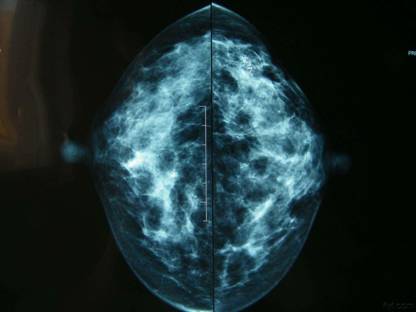

在乳房X光片中,乳房的各部分结构会以黑白相间的影像显示出来,白色的部分主要是乳腺导管和纤维结缔组织,相对模糊的灰色或黑色部分则是脂肪组织。

乳房病变一般呈不透光的白色。如果肉眼直接分辨得出来,则称之为高密度阴影;而白色较小,有时甚至需要借助于放大镜才能看清楚的时候,则称之为钙化。当钙化灶较细小、较密集分布时,乳腺癌的可能性比较大。

美国放射协会将正常乳腺分为4型:脂肪型(乳腺大部分组织为脂肪,透亮度较高)、少量腺体型、多量腺体型、致密型(乳腺大部分组织为腺体,非常致密,透亮度较差),其中在脂肪型的乳房中病变的发现率最高,而致密型则因为显像不清,病变的发现率较低。